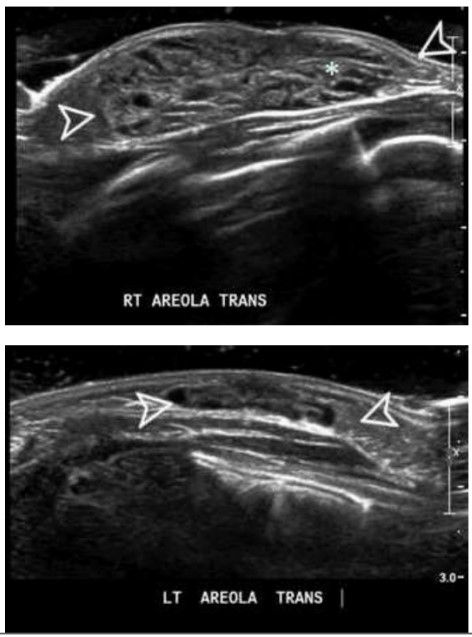

Analise o caso a seguir.

Recém-nascida (RN) do sexo feminino, com 10 dias de vida é levada ao consultório com aumento unilateral da mama direita, sem outras queixas (vide abaixo). A mãe nega comorbidades clinicas ou alterações durante a gestação e o parto.

A conduta recomendada para esse caso é a